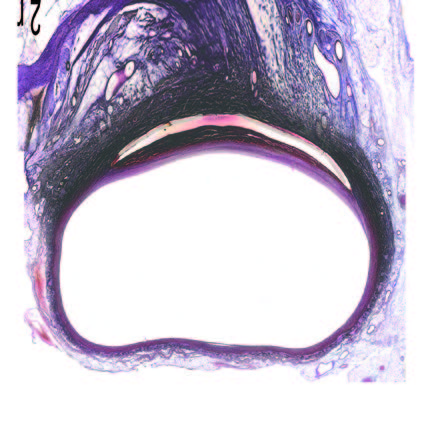

Ultra-low profile patch, rapidly endothelialised¹

Implant fully absorbed within 180 days¹

Abluminal surface matrix promotes adherence and healing¹